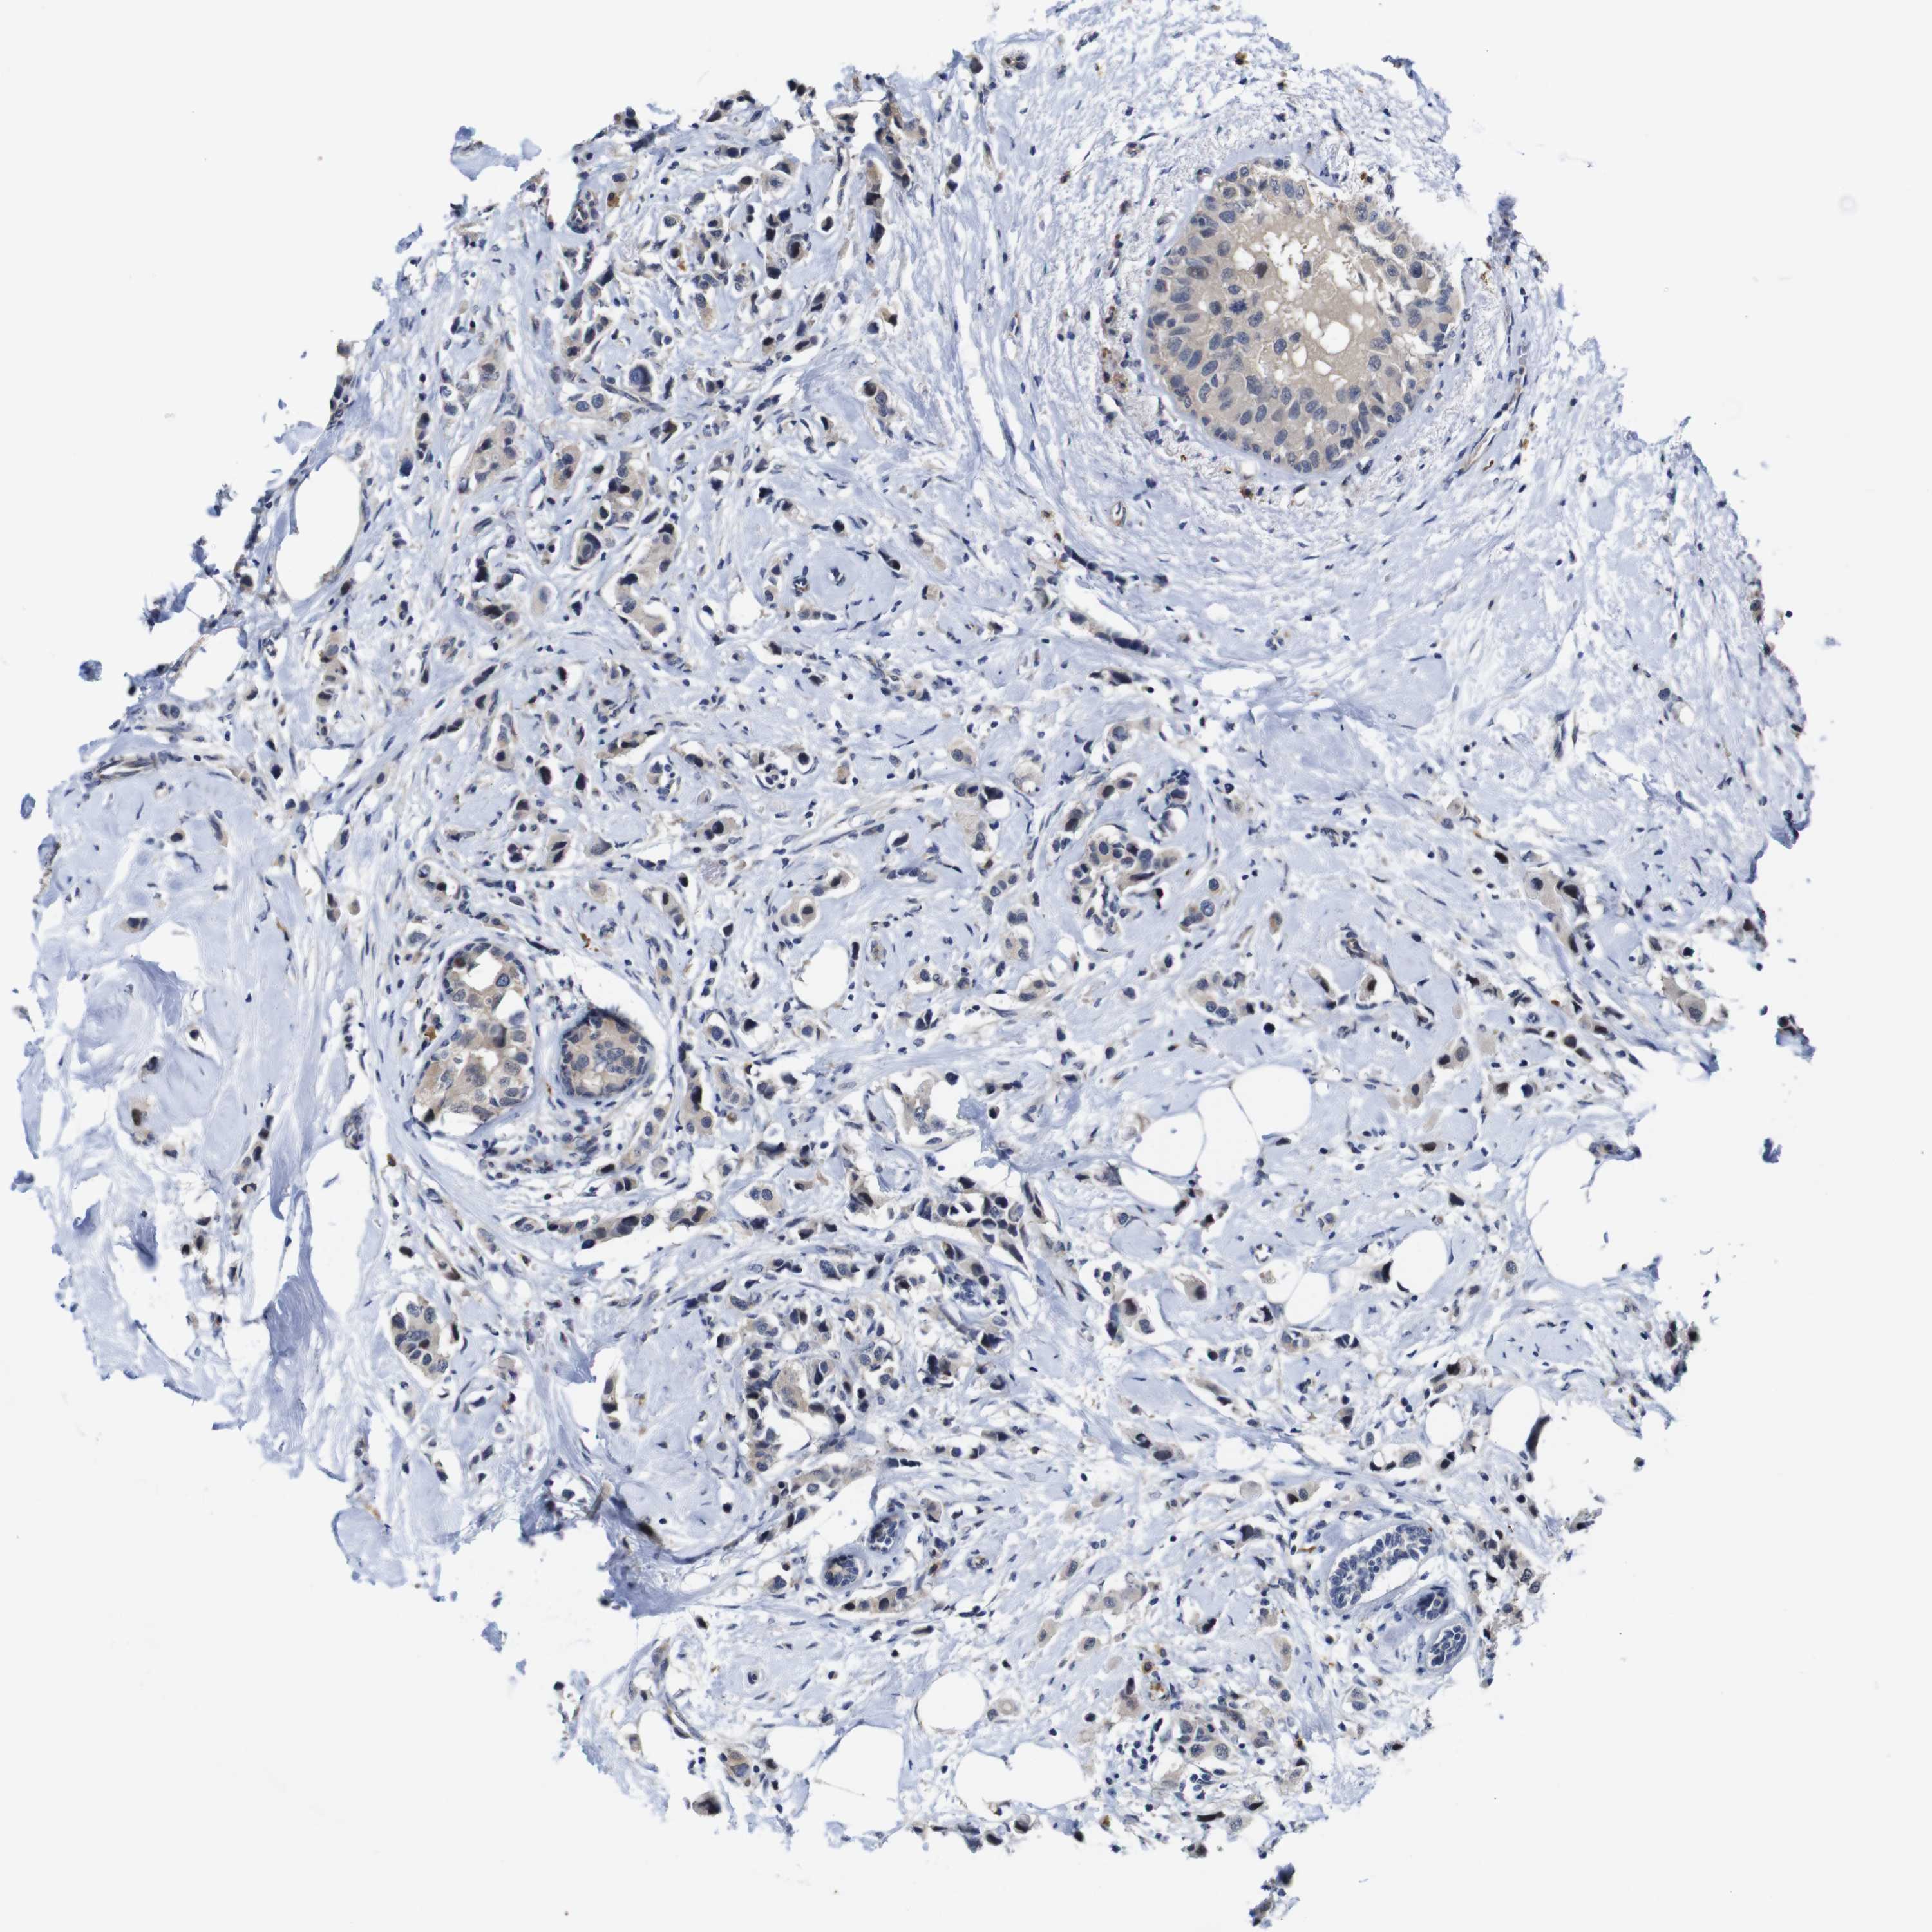

CANCER BREAST CANCER Show tissue menu

BRCA TCGA BRCA VALIDATION PROTEIN EXPRESSION

ANTIBODIES

AND

VALIDATION